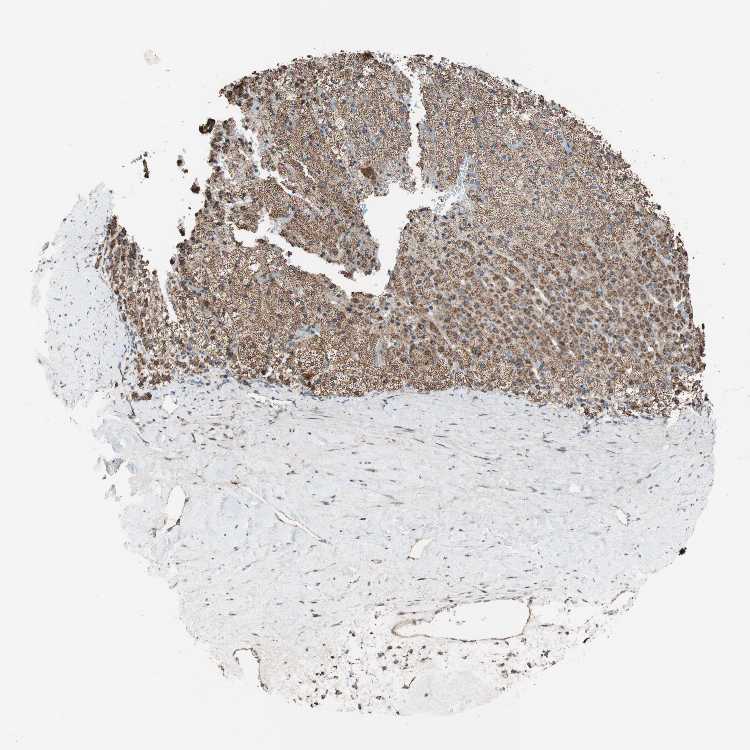

ADRENAL GLAND - Antibody stainingi

Antibody staining in the annotated cell types in the current human tissue is reported as not detected, low, medium, or high, based on conventional immunohistochemistry profiling in selected tissues. This score is based on the combination of the staining intensity and fraction of stained cells.

Each image is clickable and will lead to virtual microscopy that enables deeper exploration of all samples and also displays staining intensity scores, fraction scores and subcellular localization as well as patient and tissue information for each sample.

Antibody HPA005572

Glandular cells High